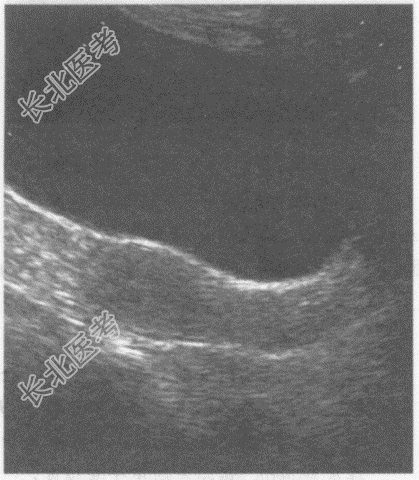

- 单项选择题临床资料:女, 60岁,绝经6年, 常规体检。

超声综合描述:子宫前位, 测值减小,肌层回声均匀, 宫内膜显示不清。

其超声提示: A、绝经后子宫萎缩

B、子宫增大

C、正常子宫

D、子宫内膜增生

E、子宫腺肌症